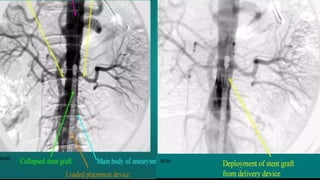

• Once vascular access is established and landmarks for positioning the device are obtain with angio, the main

device is positioned with particular attention paid to the location of the opening for the contralateral iliac limb (“

contralateral gate”)

• The aortic neck is imaged, slight degree of craniocaudal and left anterior oblique angulation may improve imaging

of the renal ostia

• With the proximal radiopaque markers of the graft positioned appropriately

• The body of the graft is deployed

• A guidewire is advanced through the contralateral access site into the contralateral gate

• Once the contralateral guidewire is positioned within the main body of the endograft, the deployment of the

endograft at the neck of the aneurysm is completed followed by deployment of the contralateral

• Once the Endograft component are in place, the attachment sites and endograft junctions are gently angioplastied with a

compliant or semi compliant balloon

• Completion angiography is performed to evaluate the patency of the renal arteries and evaluate for endoleak